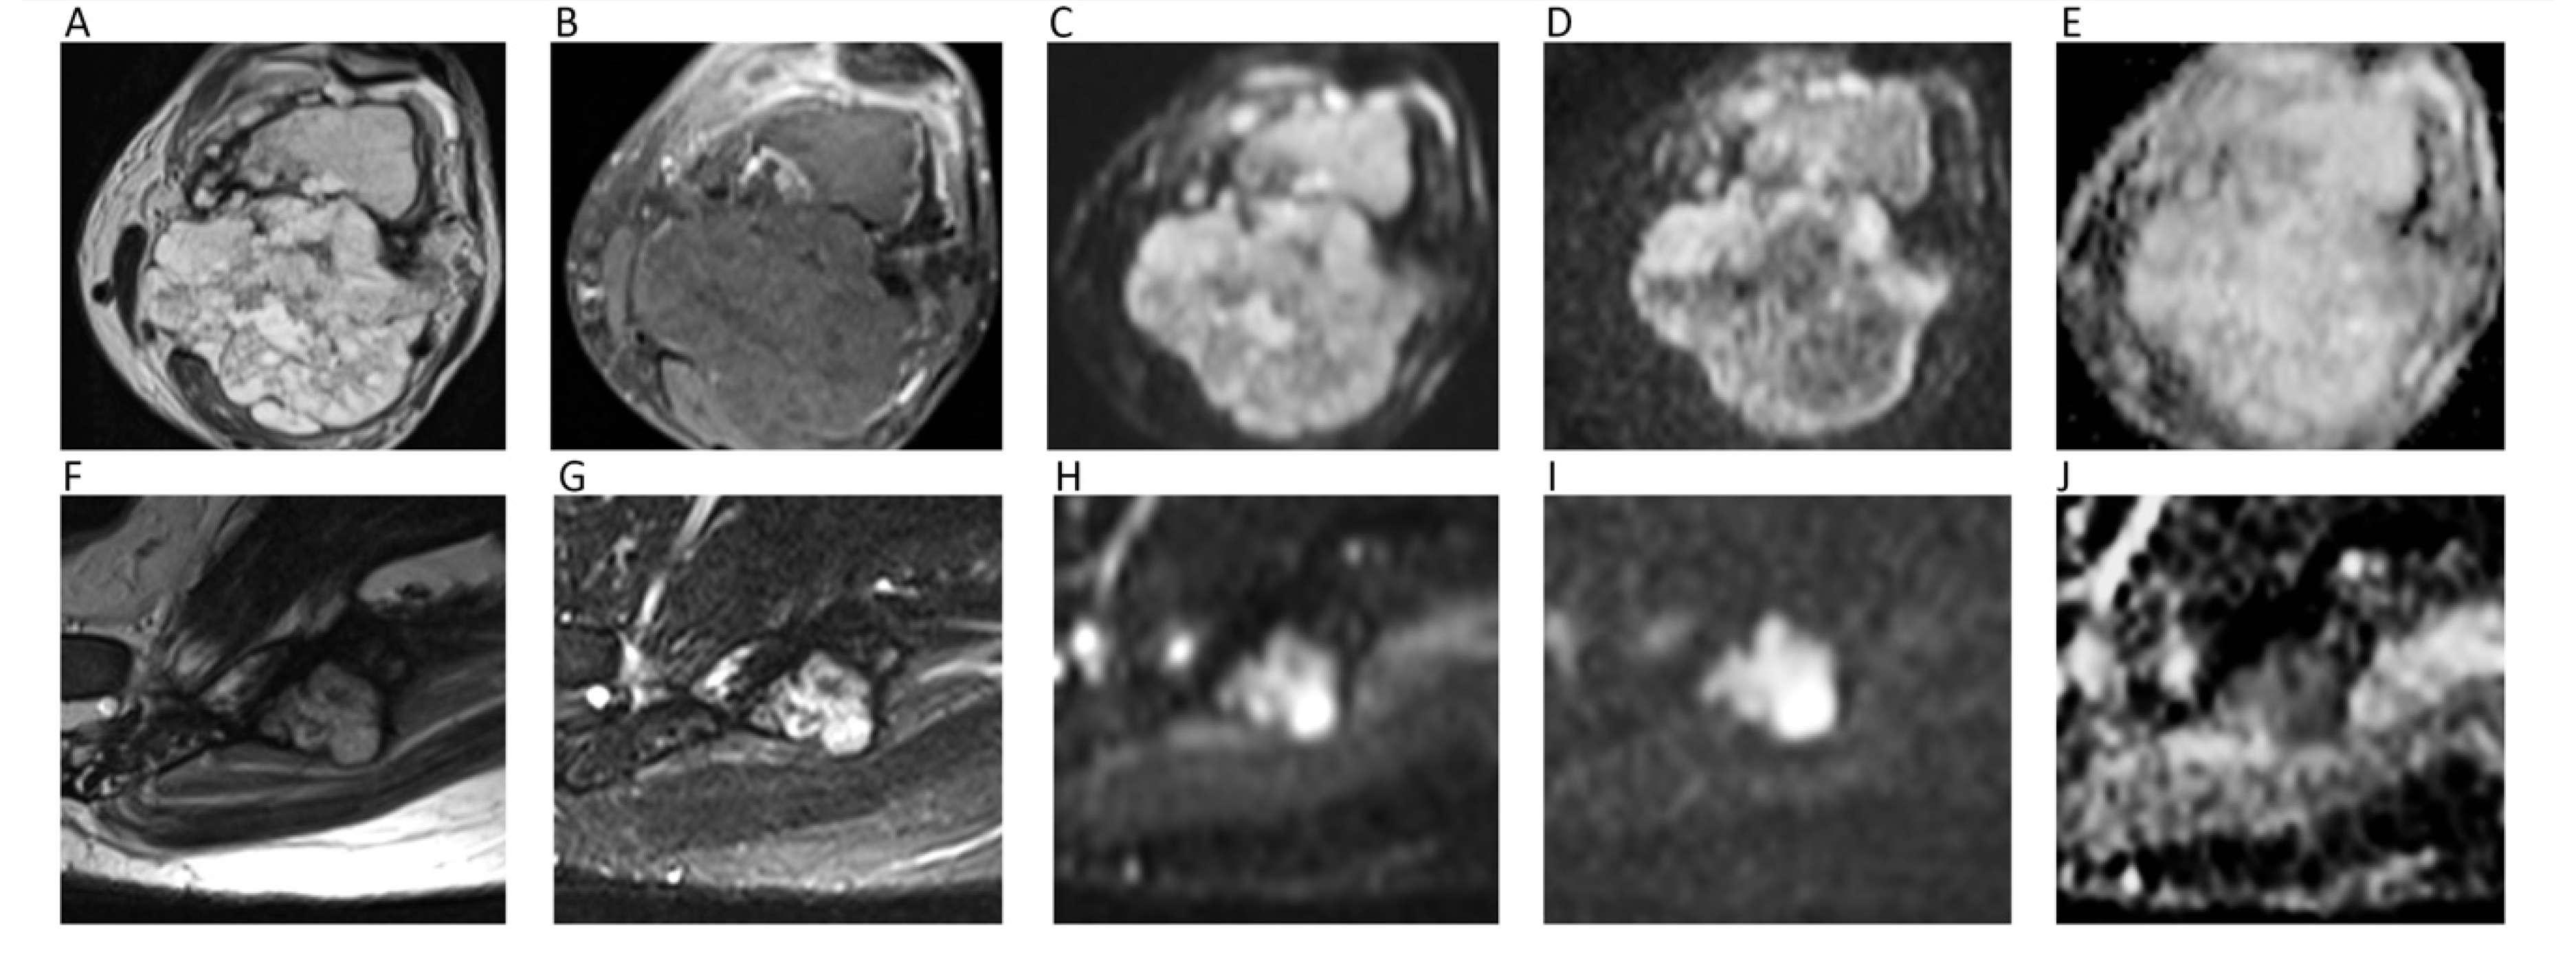

13. Bone Tumors

14. Soft Tissue Tumors

| Bone Tumors | Wang, T.; et al. World J. Surg. Oncol. 2014 [96] | Retrospective; 187 patients; 3.0T MRI. | Mean ADC (×10−3 mm2/s) of benign tumors (1.17 ± 0.36) significantly higher than that of malignant (0.87 ± 0.20). |

| Soft Tissue Tumors | Choi, Y.J.; et al. J. Magn. Reson. Imaging 2019 [107] | Retrospective; 136 patients; 3.0T MRI. | Significant difference between mean ADC (×10−3 mm2/s) of benign (1.44 ± 0.46) and malignant (0.9 ± 0.40) soft tissue tumors. |